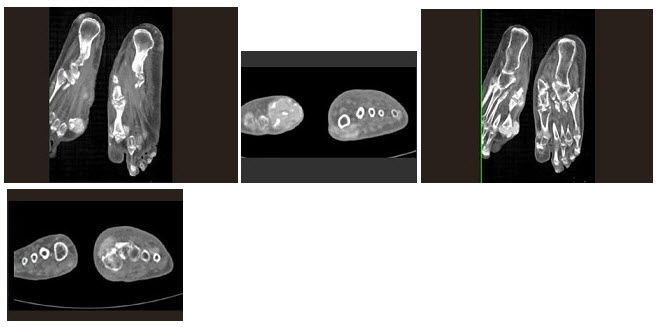

男,11岁,持续性右足部疼痛,无发热。根据右足正、斜位X线片及CT平扫片,最可能的诊断为()

A.骨样骨瘤

B.疲劳性骨折

C.尤文肉瘤

D.骨软骨瘤

E.硬化性骨髓炎